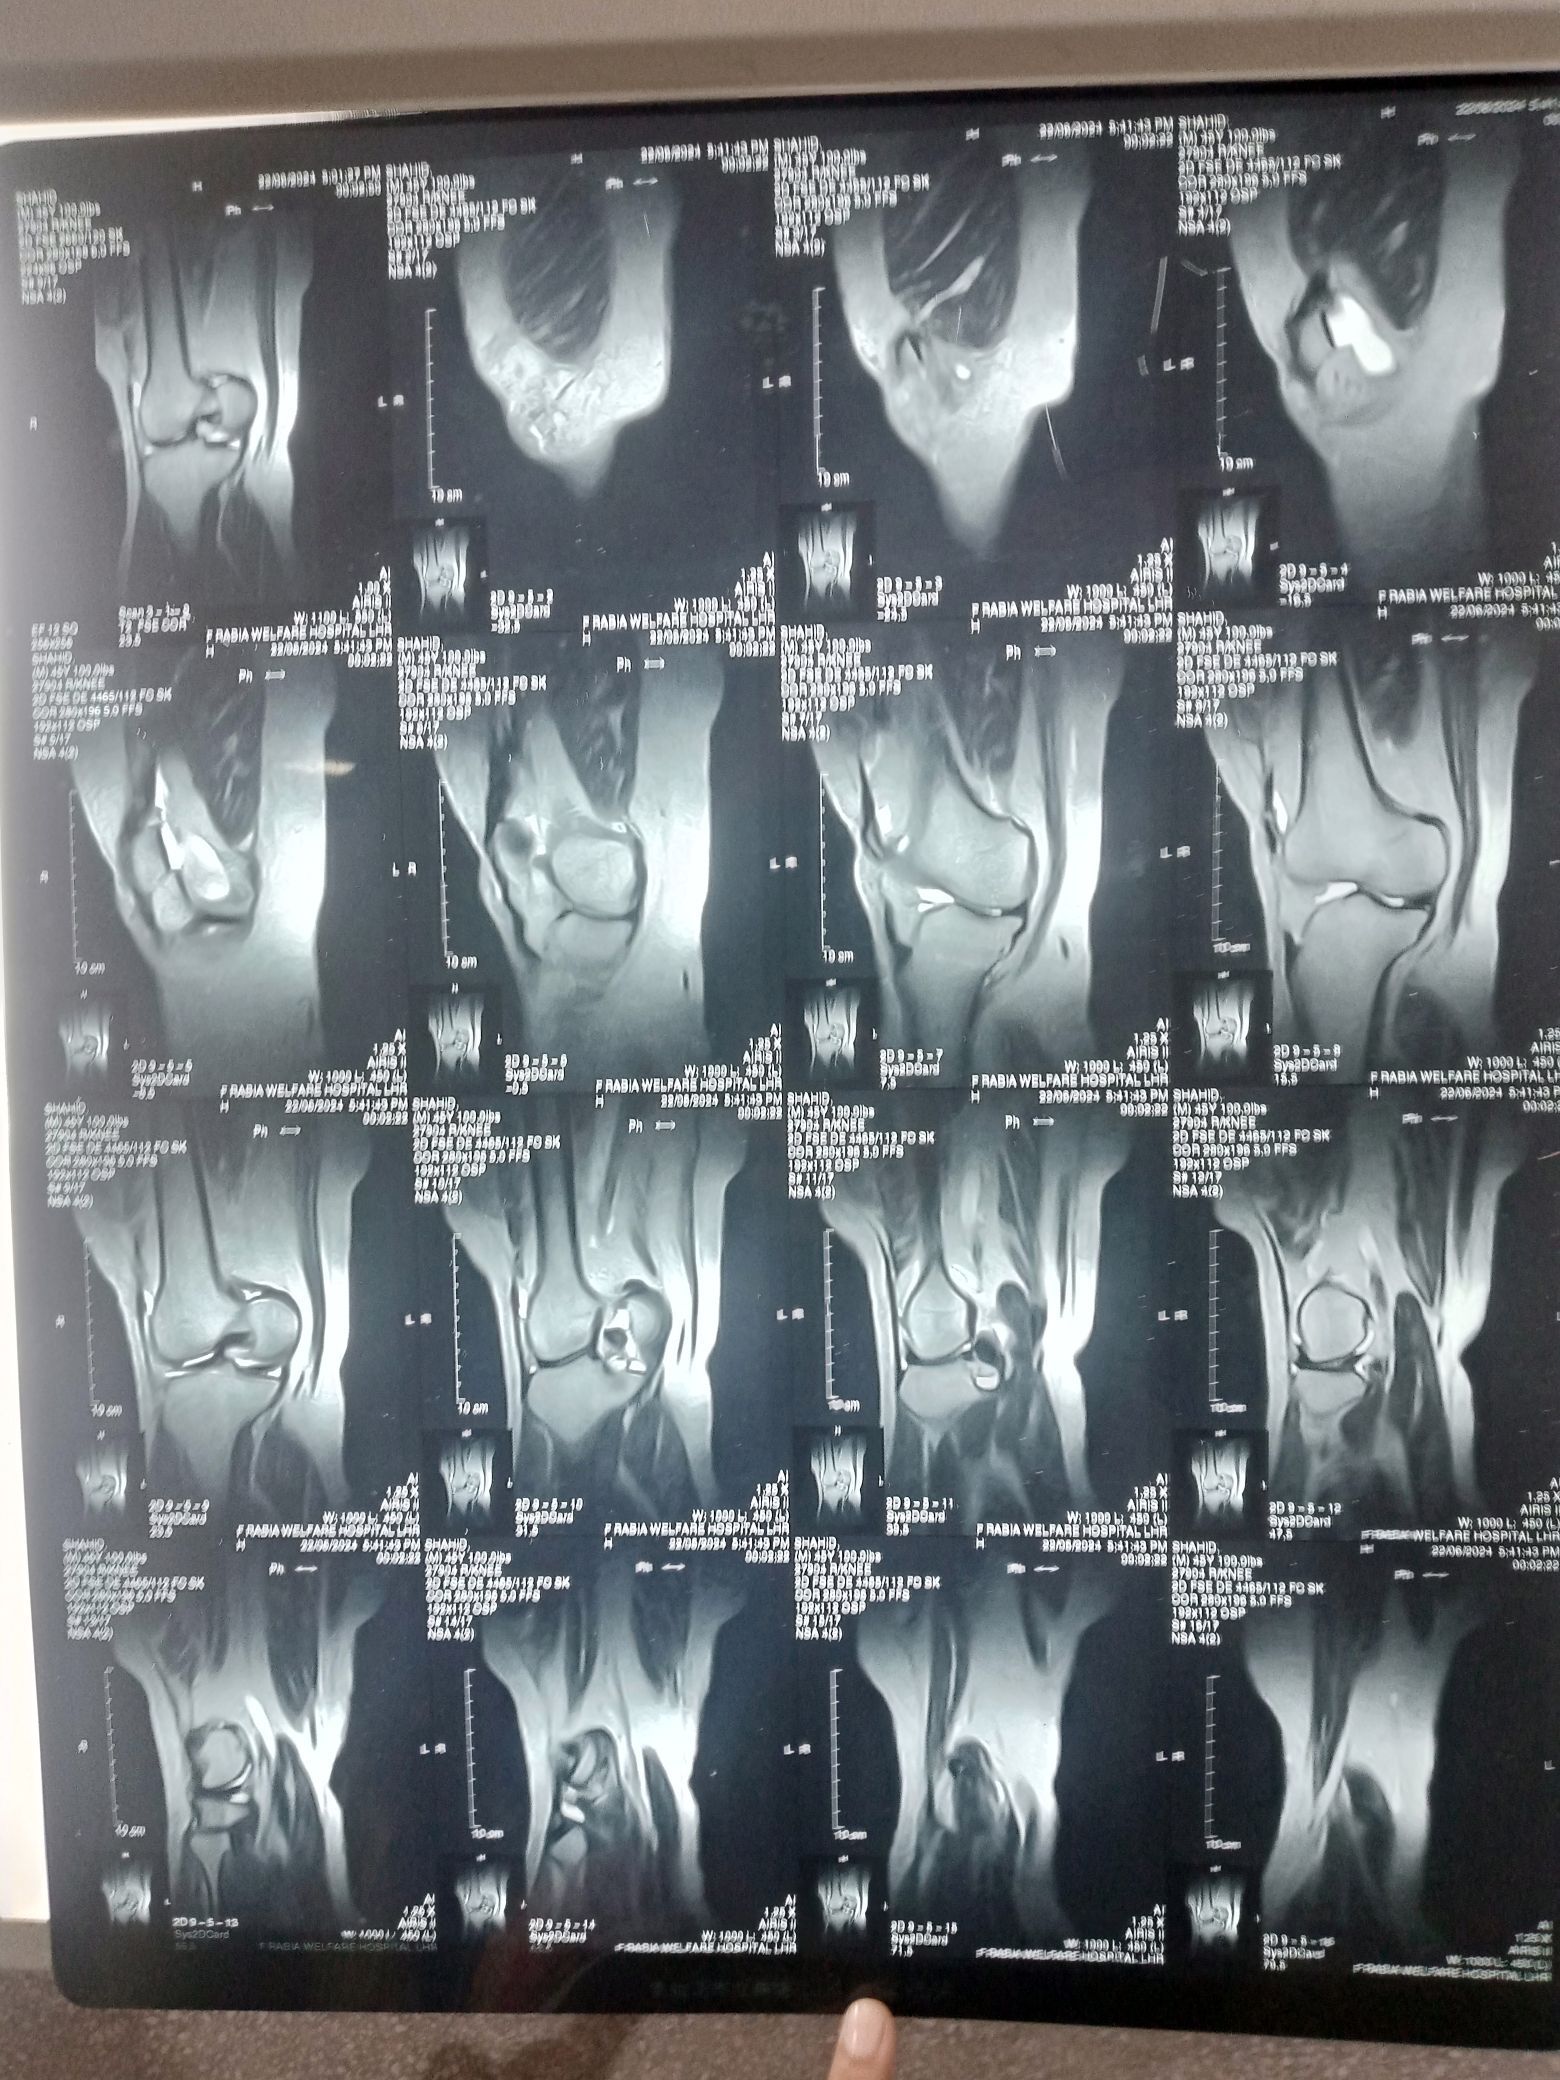

ACL injury

Acl

Knee Joint

Posttraumatic

How to Read Knee MRI of ACL Tear